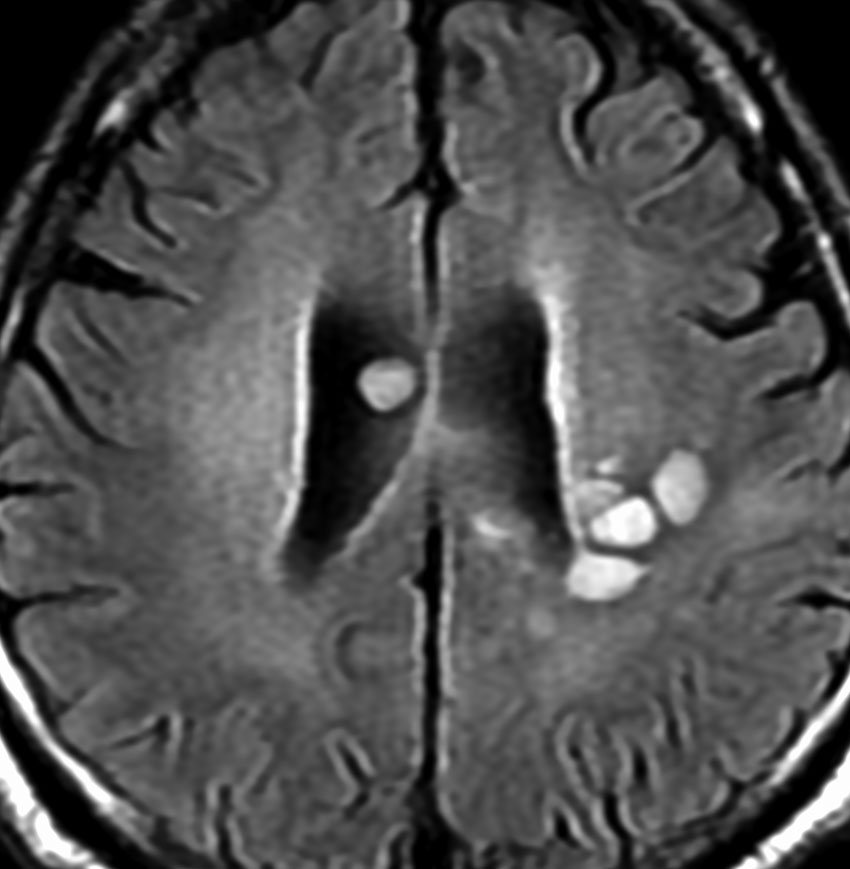

MRI画像所見 60代で嚥下障害と構音障害で発症した例

延髄から中脳まで腫瘍があって脳幹部が腫れています。この画像ですと,小児のびまん性橋膠腫(DIPG,びまん性正中グリオーマ)のように見えます

両側視床から大脳基底核,両側大脳半球深部白質,脳梁まで広範囲に腫瘍が存在します。退形成性星細胞腫のようにまだらにガドリニウム増強されます。